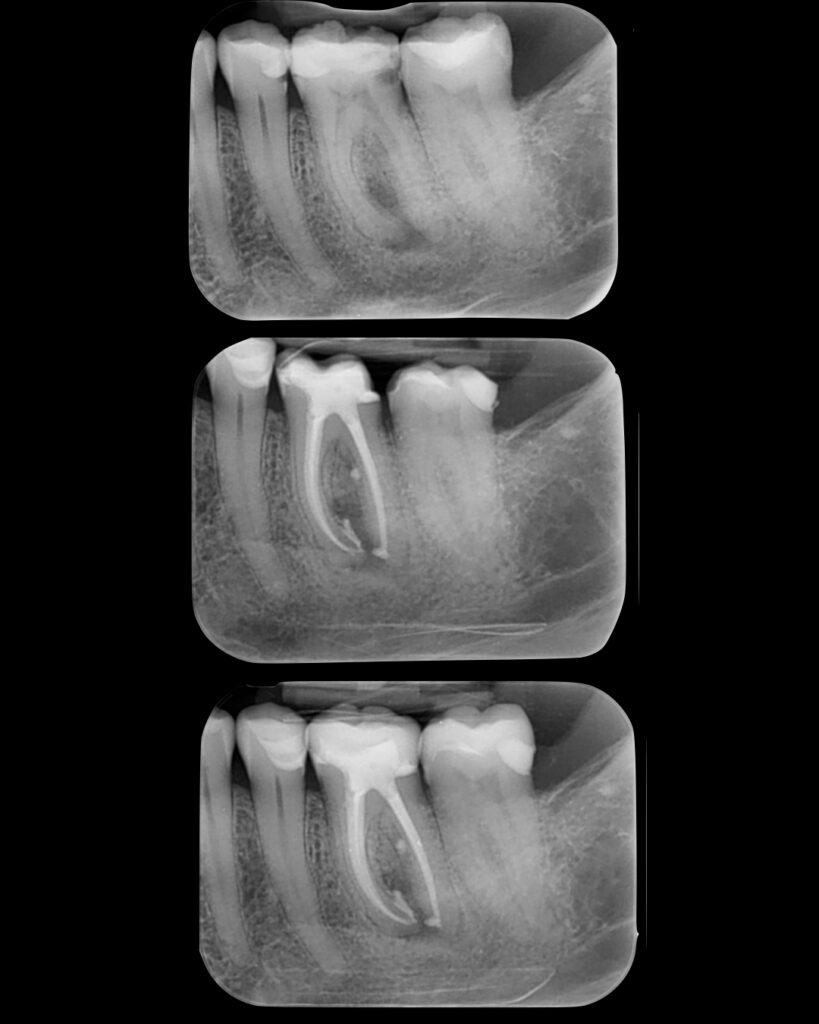

Tooth 3.6 was severely compromised and was managed with endodontic treatment, deep margin elevation, and an indirect adhesive restoration with full cuspal coverage using a lithium disilicate overlay.

Tooth 3.7 presented a large MOD carious lesion, with both distal cusps and the mesiolingual cusp structurally compromised.

Endodontic treatment was performed using nickel–titanium rotary instrumentation, with irrigation protocols including sodium hypochlorite and 17% EDTA, both sonically activated.

The root canal system was obturated using a single-cone cold technique with a bioceramic sealer.

Now we wait for healing 🤞